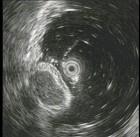

问题 女,28岁,间歇性上腹痛腹胀4年,无呕吐。抗酸制剂治疗无效,查体上腹轻压痛,B超肝查未见异常,胃镜检查如图。最有可能性的诊断是 ( )

选项 A.消化性溃疡 B.胃癌 C.胆囊炎 D.胃下垂 E.萎缩性胃炎

答案 D